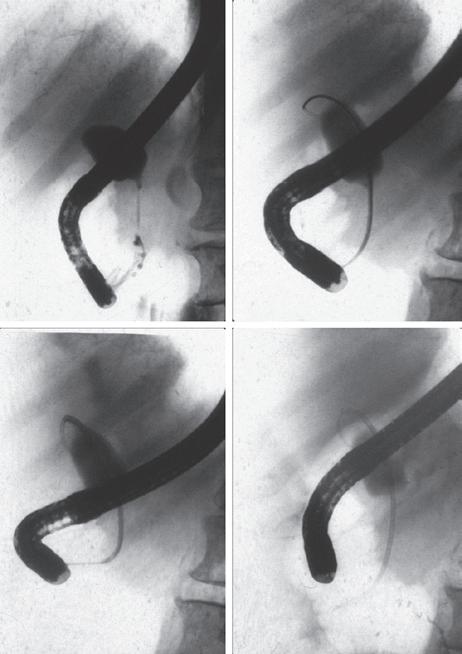

FIG 1.3 The endoscopic and fluoroscopic images from the first sphincterotomy performed by Drs. Nakajima and Kawai in Kyoto, Japan, in 1974. Clockwise from left: The fluoroscopic images on the left show the distal bile duct calculus (arrow) with upstream filling of the bile duct. The catheter was used for cannulation and sphincterotomy. On the right, the cholangiogram and pancreatogram revealing bile duct clear of filling defect.